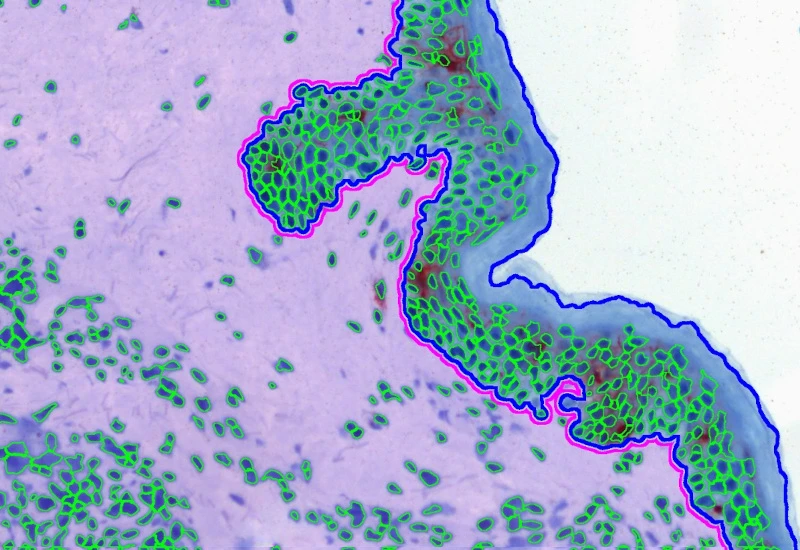

The IHC Macrophages App detects macrophages based on adequately stained IHC samples (e.g. CD68). The App further proves area detection and distance range algorithms to determine the distance of Langerhans cells from the border of the epidermis within and without. Each segmented cell compartment is measured for up to 20 parameters, as is the distance of each cell to the boundary.

Dermis and epidermis detection

Combined detection